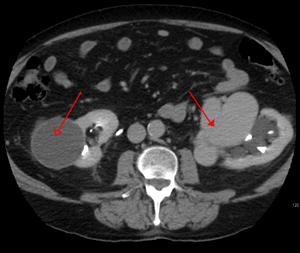

يتم تشخيص التشوه الشرياني الوريدي بشكل أساسي من خلال طرق التصوير التالية:

- التصوير المقطعي المحوسب (CT) هو عبارة عن أشعة سينية غير باضعة لعرض الهياكل التشريحية داخل الدماغ لاكتشاف الدم في الدماغ أو حوله. تتضمن تقنية أحدث تسمى تصوير الأوعية المقطعية المحوسبة حقن التباين في مجرى الدم لعرض شرايين الدماغ. يوفر هذا النوع من الاختبارات أفضل صور الأوعية الدموية من خلال تصوير الأوعية والأنسجة الرخوة من خلال التصوير المقطعي المحوسب.